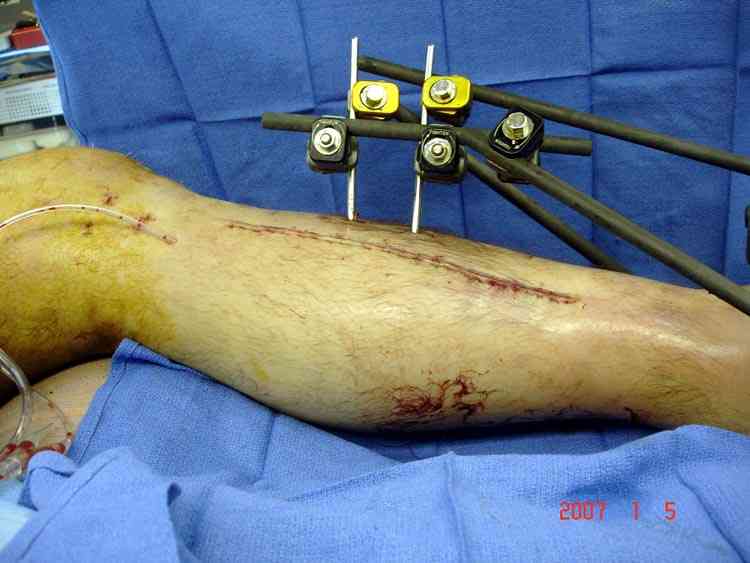

Отечность в зоне фиксации является противопоказанием к открытому методу. Для профилактики осложнений с фиксацией можно повременить применением стабилизирующего наружного фиксатора. Фиксатор восстанавливает длину конечности, облегчает в будущем репозицию и создает благоприятные условии для спадения отека. Также позволяет экономить средства, вместо дорогого стационара больной может находится на амбулаторном наблюдении. Появление симптома "skin wrinkle test" (морщинки) подскажет о готовности кожного покрова для окончательной операции на костях.

В ежедневной практике применяем методику приближения краев раны с помощью недорогих эластических сосудистых держалок, которые под натяжением резины сближают края. Такая методика закрытия раны оберегает от чрезмерного увлечения кожной пластикой.

На сегодня существует множество различных механических приспособлений, которые работают на принципе медленного сближения краев ран.

На фото результат от Derma Closure, аппарата, предназначенного для трудно закрываемых дефектов кожных покровов.

Множественная огнестрельная травма конечностей, перелом костей предплечья, фиксация в первые часы и дефект мягких тканей, мероприятия по закрытию...